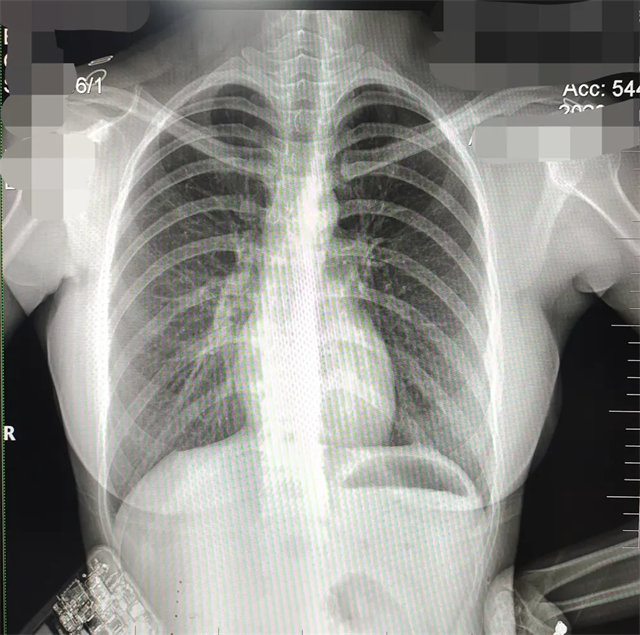

缺陷:双侧胸锁关节不对称,且有手机显影。

解决:去除手机后,使患者左侧紧贴成像件曝光。